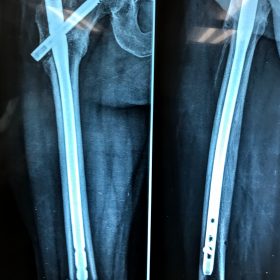

Διατροχαντήριο : Εξωαρθρικό κάταγμα, στην περιοχή ανάμεσα στο ελάσσονα και το μείζονα τροχαντήρα. Αντιμετωπίζεται χειρουργικά με ενδομυελική ήλωση τύπου γ-Nail. Δύο τομές 3 εκατοστών και 1 εκατοστού αντιστοίχως για την εισαγωγή και το κλείδωμα του ήλου μέσα στο οστό. Η μέθοδος είναι κλειστή,σχεδόν αναίμακτη,διάρκειας 30 λεπτών,με τη βοήθεια C-ARM (τηλεόρασης). Στον ασθενή παρέχεται οπτικό υλικό (όλα τα χειρουργικά στάδια) σε CD ή Στικάκι,λόγω της δυνατότητας καταγραφής του χειρουργείου από το C-ARM Ο ασθενής περπατάει άμεσα μετεγχειρητικά στις 5 ώρες μετά την επέμβαση και εξέρχεται από το νοσοκομείο σε 1 -2 ημέρες.

Υποτροχαντήριο :Εξωαρθρικό κάταγμα κάτω από τον ελάσσονα τροχαντήρα του μηριαίου οστού. Αντιμετωπίζεται χειρουργικά με ενδομυελική ήλωση τύπου Long γ-Nail. Δύο τομές 3 εκατοστών και 1 εκατοστού αντιστοίχως για την εισαγωγή και το κλείδωμα του ήλου μέσα στο οστό. Η μέθοδος είναι κλειστή,σχεδόν αναίμακτη,διάρκειας 60 λεπτών,με τη βοήθεια C-ARM (τηλεόρασης). Στον ασθενή παρέχεται οπτικό υλικό (όλα τα χειρουργικά στάδια) σε CD ή Στικάκι,λόγω της δυνατότητας καταγραφής του χειρουργείου από το C-ARM Ο ασθενής περπατάει άμεσα μετεγχειρητικά στις 5 ώρες μετά την επέμβαση και εξέρχεται από το νοσοκομείο σε 1 -2 ημέρες.